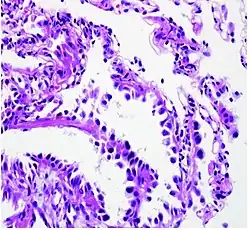

.jpg)

The majority of lung cancers can be characterized as either small cell lung cancer (SCLC) or non-small cell lung cancer (NSCLC). Lung adenocarcinoma is one of the three major subtypes of NSCLC, which also include squamous carcinoma and large cell carcinoma.[15]